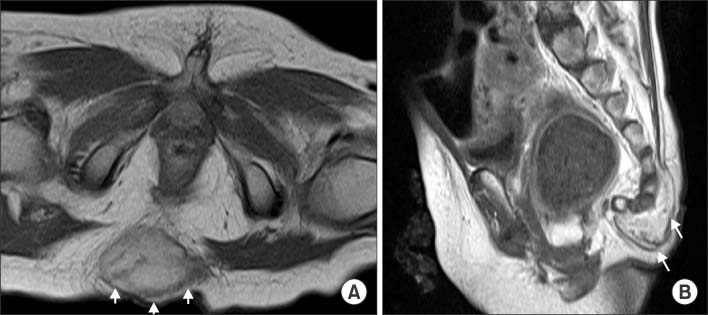

She visited a pediatric neurosurgery outpatient clinic at 11 months after birth because of multiple systemic granulomas and a sacrococcygeal mass. T1-weighted magnetic resonance imaging showed a subcutaneous enhancing lesion (3.0×2.0×3.4 cm) at the sacrococcygeal level (Fig. 1). She was transferred to our department with a suspicion of sacrococcygeal teratoma. She underwent surgery, and the mass was completely resected at 13 months of age. On pathological examination, we diagnosed the mass as malignant EHE. There were regions with diffusely infiltrating epithelioid cells, and we noted epithelioid markers, such as CD31 and Fli-1, in the mass. Additionally, nuclear pleomorphism and mitosis were noted, with a high Ki-67 index, which suggested malignancy.

Fig. 1

T1-weighted magnetic resonance images. A mass-like subcutaneous enhancing lesion (3.0×2.0×3.4 cm, white arrows) is seen at the sacrococcygeal level. (A) Transverse view. (B) Sagittal view.

Fig. 1 T1-weighted magnetic resonance images. A mass-like subcutaneous enhancing lesion (3.0×2.0×3.4 cm, white arrows) is seen at the sacrococcygeal level. (A) Transverse view. (B) Sagittal view.